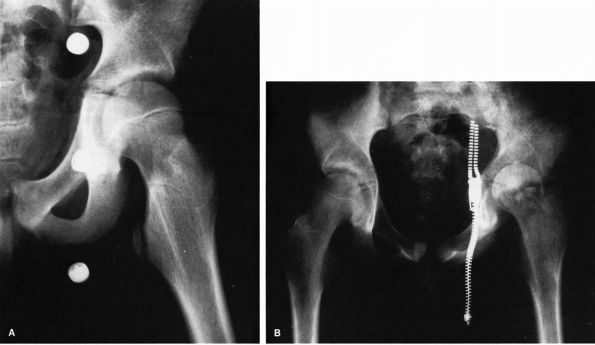

itself, producing complete growth arrest (Figure 5-3).

This is most likely to occur in the proximal femur, where the result is

![]() |

FIGURE 5-3.

AP radiograph of the pelvis of a 1-year-old girl who had an osteomyelitis of the proximal femur and a septic arthritis of the hip as a neonate. These infections resulted in destruction of the physis and the epiphysis. |